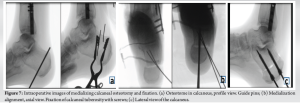

The causative fracture was a left tibia-fibula fracture in early childhood due to a road traffic accident, treated conservatively with casting. The lateral malleolar fracture was insufficiently reduced, resulting in significant fibular shortening. The 57-year-old patient presented with chronic lateral-dorsal pain in the left ankle, clinically accompanied by hindfoot valgus deformity and limited mobility with a submalleolar and anterior ankle impingement. The X-rays show bone remodeling and tibiofibular arthrodesis at the distal third (Fig. 1). Additional imaging included scintigraphy showing progressive tibio-talar osteoarthritis and early-stage Lisfranc joint osteoarthritis (Fig. 2). MRI and CT confirmed post-traumatic fibular shortening, consequent hindfoot valgus, and partially misaligned tibio-talar osteoarthritis in the lateral compartment (Figs. 3-5). Surgical management was indicated for the angular malunion, involving medializing calcaneal osteotomy and fibular lengthening osteotomy on the left ankle. Preoperative planning included standing anteroposterior (AP) and lateral radiographs of the ankle and hindfoot, as well as hindfoot alignment views (Saltzman view) to assess coronal malalignment. Full-length standing radiographs of both lower limbs were obtained to evaluate the mechanical axis. CT scan was used to precisely measure the degree of fibular shortening and tibiofibular joint fusion. MRI allowed for soft tissue and cartilage evaluation, particularly at the tibio-talar joint. Fibular shortening was assessed by comparing the level of the lateral malleolus to the plafond tibial and to the medial malleolus on the contralateral, uninjured side. Correction planning aimed to restore the fibular length to reestablish the normal relationship, targeting the lateral malleolus tip approximately 5–7 mm distal to the talar dome on the mortise view, which corresponds to the physiological fibular station. Angular correction involved planning for a 10° medial translation at the calcaneus level to correct the hindfoot valgus, based on hindfoot alignment measurements. Five weeks later, arthroscopy was performed for osteophyte removal as a second stage. The surgical procedure involved a Z-lengthening osteotomy of the , achieving approximately 9 mm of lengthening, fixed with two compression screws and a neutralization plate, supplemented by a corticocancellous graft harvested from the left anterior iliac crest (Fig. 6). The medializing calcaneal osteotomy required a medial displacement of the large tuberosity by 10 . The 10-mm medial shift was determined based on hindfoot alignment analysis, correcting approximately 1 mm/degree of valgus. This was achieved through lateral cortical osteotomy with the saw and medial completion with an osteotome, then fixed with two partially threaded titanium 7.0 compression screws (FixosR, Stryker, Mahwah, NJ 07430 USA) (Fig. 7). The surgery was performed under scopic guidance. Postoperatively, the non-weight-bearing period extended to 5 weeks, followed by an arthroscopy for osteophyte removal performed after the cast immobilization period. Physiotherapy was initiated 2 weeks later, following suture removal, with full weight-bearing allowed using a stabilizing ankle brace. No intra-operative or early postoperative complications were reported. Postoperative radiographs obtained at 6 weeks and at the final follow-up (24 weeks) illustrate satisfactory healing and a favorable clinical outcome (Fig. 8).